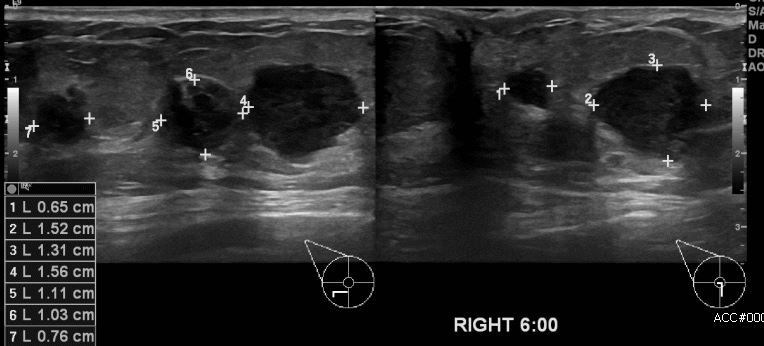

우측유방에 멍울로 내원하신 70대 환자 분으로 우측유방 6시 방향에 의심스러운 멍울

조직검사 시행하여 추측 침윤성 유관암 진단 되었습니다.